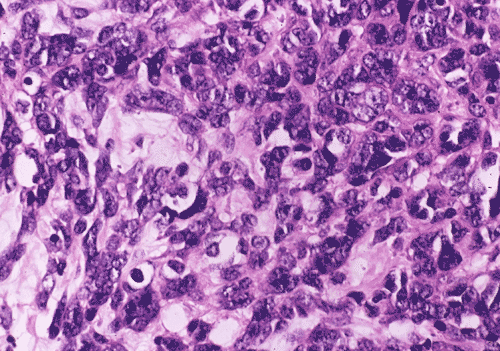

At low power magnification (Panel A and B), the tumor seems to have two distinct components. The first is a highly cellular, basophilic, background stroma. The second is islands of well-demarcated, pale bluish chondroid, hypocellular areas reminiscent of hyaline cartilage. Together, these two components impart a so-called "white clouds in blue sky" histologic appearance. At medium- and high power magnification (Panel C and D), the lacuna in the chondroid areas are well appreciated which helps to confirm the cartilaginous nature of these pale islands. Please note the impressive nuclear pleomorphism in the neoplastic chondrocytes (Panel D).

The basophilic background is composed of tightly packed, undifferentiated spindle cells without significant deposition of collagen fibers in between (Panel E). Panels  F, G, and H are taken from a different area of the tumor and were not posted on the question web-page. The pathologic change in these areas are very common among mesenchymal chondrosarcoma and should be looked. These include lobules of highly cellular tumor separated by fibrous connective tissue septa (Panel F) and Prominent tumor vascularity with highly branching vessels which (with a bit of imagination!) resemble deer "antlers" or "staghorns"(Panel G and H). This pattern of vessel distribution is similar to that seen in hemangiopericytoma (an uncommon soft tissue tumor) and is therefore often described as a “hemangiopericytoma-like” vascular pattern. The overall gross and light microscopic features in this case are consistent with a diagnosis of primary extraskeletal mesenchymal chondrosarcoma.

Grossly, mesenchymal chondrosarcoma typically appears as a circumscribed, lobulated, solid mass with a soft, fleshy, grey-white to gray-pink cut surface. Scattered deposits of cartilage and/or bone of varying size may be grossly recognized, and areas of hemorrhage and necrosis may be present. Tumor size is variable with reported tumor diameters ranging from 3 - 37 cm. Microscopically, mesenchymal chondrosarcomas are biphasic tumors composed of sheets of round to spindle-shaped primitive mesenchymal cells surrounding discrete islands of hyaline cartilage. The proportions of primitive and cartilaginous elements vary widely among tumors and even within different areas of the same tumor. Cartilaginous differentiation ranges in degree and extent from small foci with high-grade nuclear features to large areas of well-differentiated cartilage. The primitive mesenchymal component is highly vascular, typically containing large numbers of highly branched vascular channels (the so-called “hemangiopericytoma-like pattern”).